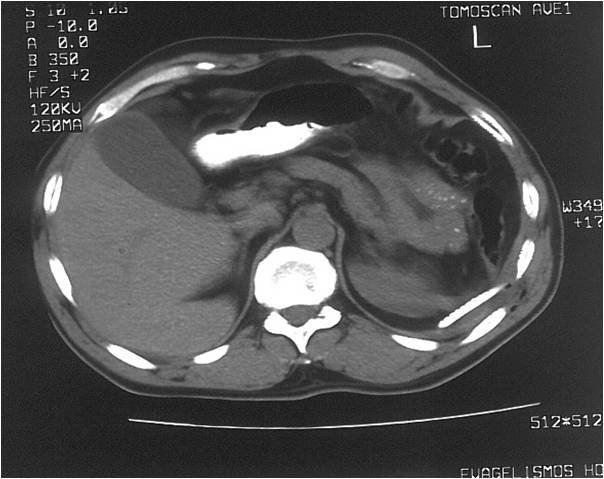

- Post splenectomy abscess

- Successful drainage